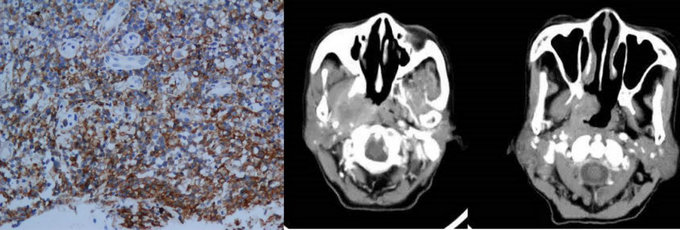

NK/T淋巴瘤病理及影像表現